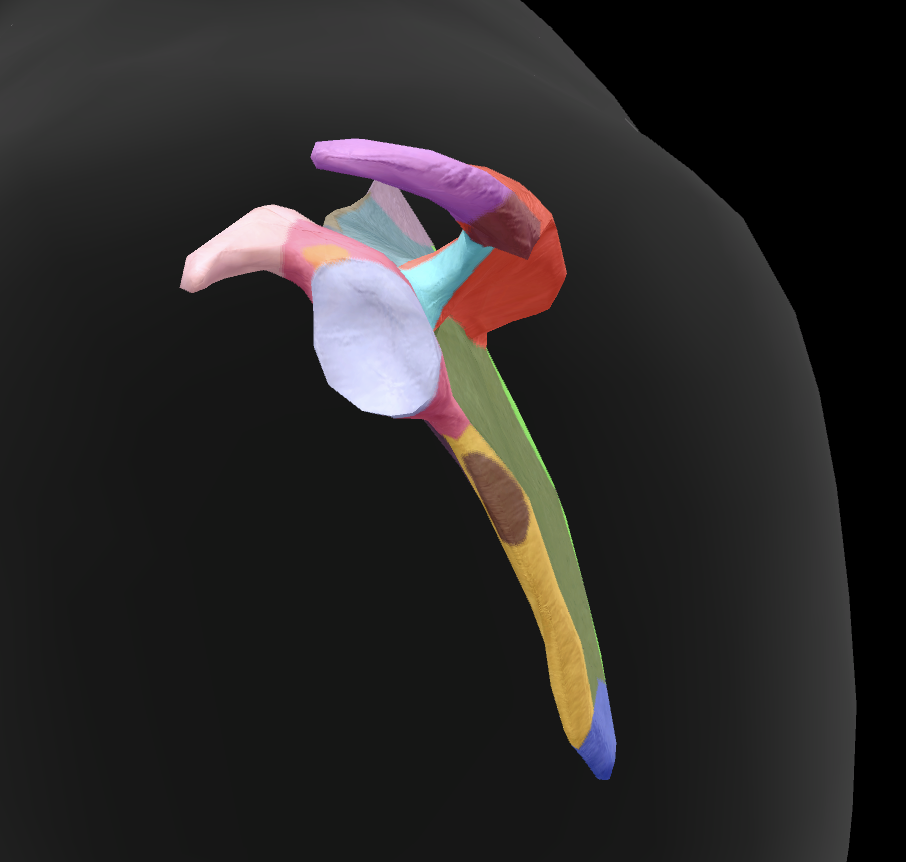

scapula

What is this boney landmark?

spine of scapula

What is this boney landmark?

supraspinous fossa

What is this boney landmark?

infraspinous fossa

What is this boney landmark?

acromion process

What is this boney landmark?

superior angle

What is this boney landmark?

inferior angle

What is this boney landmark?

lateral border

What is this boney landmark?

medial border

What is this boney landmark?

subscapular fossa

What is this boney landmark?

spinoglenoid notch

What is this boney landmark?

glenoid fossa

What is this boney landmark?

supraglenoid tubercle

What is this boney landmark?

infraglenoid tubercle

What is this boney landmark?

coracoid process

What bone is this?

humerus

What is this boney landmark?

head

What is this boney landmark?

anatomical neck

What is this boney landmark?

surgical neck

What is this boney landmark?

lesser tubercle

What is this boney landmark?

bicipital grove

What is this boney landmark?

deltoid tuberosity

What is this boney landmark?

shaft

What is this boney landmark?

capitulum

What is this boney landmark?

trochlea

What is this boney landmark?

radial fossa

What is this boney landmark?

coronoid fossa

What is this boney landmark?

medial epicondyle

What is this boney landmark?

lateral epicondyle

What is this boney landmark?

greater tubercle